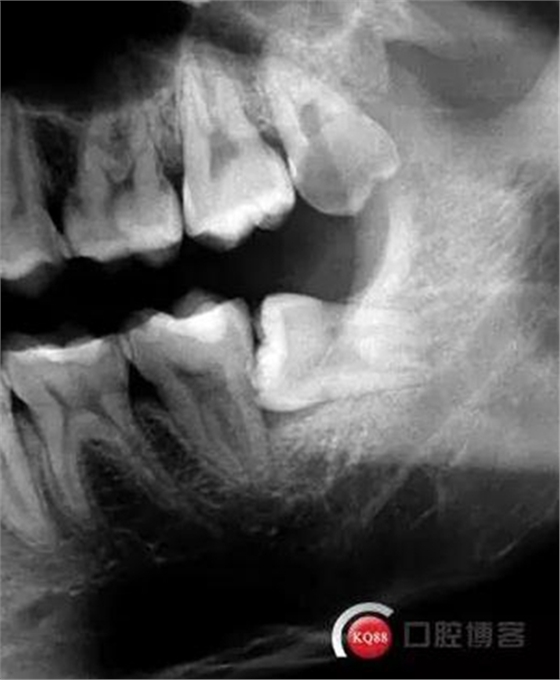

檢查:口內(nèi)可見38未完全萌出,無松動,周圍牙齦顏色正常,叩診(—)觸診(—),X線顯示近中阻生,雙根

診斷:阻生齒

治療方案:建議拔除